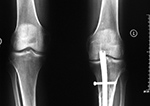

Left knee antegrade intramedullary rod displacement into knee joint |